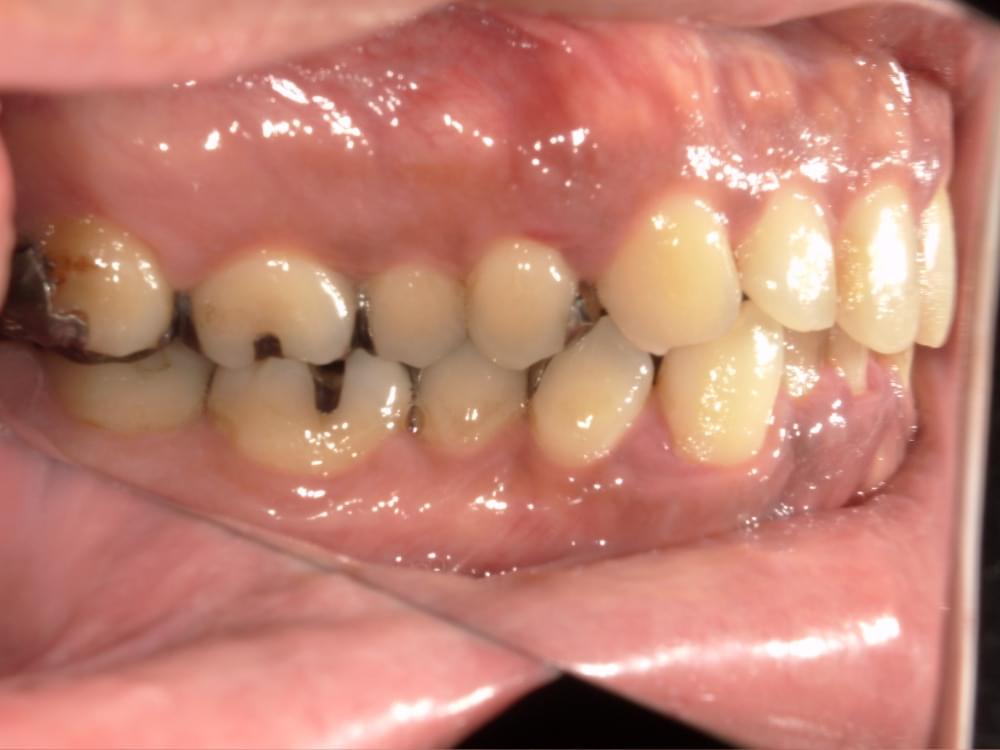

歯周病治療プログラムの治療例4

- 歯の根元が割れていると言われ抜歯が必要と言われた

- 全てのセラミックを入れている箇所で歯周病になっていると2,3年かよっているがよくならない。

せっかくセラミックを入れれば良くなるかと思ったのにショック

私(長島)からの提案として

なぜ歯周病になってしまうのかを根本的に調べたほうがいいですよと伝えた。

歯周病になってしまうのは、患者さんはブラッシング方法がダメだからっと思っている方が多いが、中にはブラッシングをあまりしなくても歯周病にならない方がいますし、逆に1日3回ブラッシングしても歯周病が改善しない方がいますので、○○さんの歯周病になった原因を特定したほうがいい。

まずは精密検査をされて、○○さんの歯周病を見つけることが最優先課題とお伝えしました。

治療の概要

治療内容

行動科学に基づき、「自分の歯は自分で守る」という意識改革や行動変容を促しながら、スケーリングや歯ブラシ・フロス指導を行いました。

治療期間・回数・時間

1.5ヶ月・5回・計5時間

費用

29,500円+税

リスク・副作用

歯肉の痛み・出血